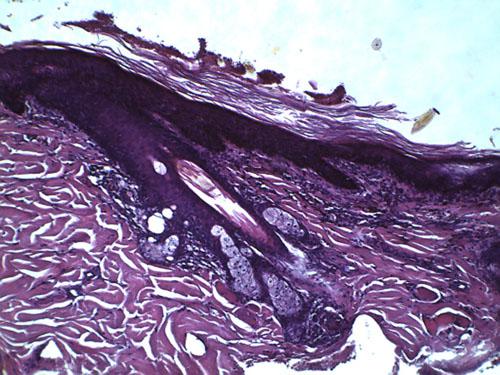

L’examen histopathologique de biopsies cutanées révèle une hyperkératose orthokératosique de la surface épidermique et des follicules pileux, ainsi qu’une mélanose dermique (photo 9).

Photo 9 : Observation microscopique (x400) d’une biopsie cutanée:

noter l’hyperkératose orthokératosique et la mélanose.